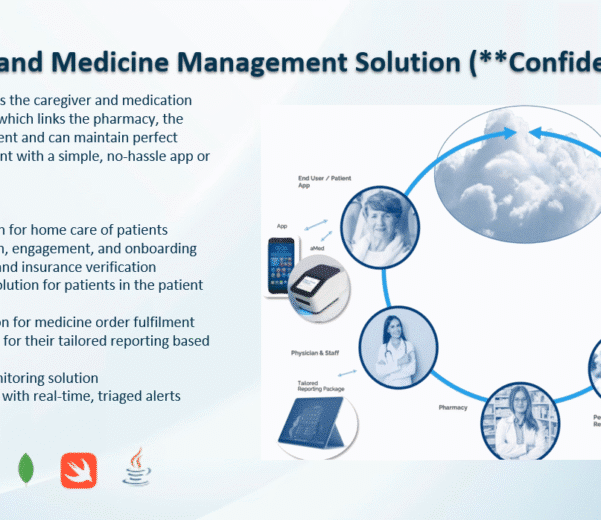

READ MORECase Study: Caregiver and Medicine

Case Study: Caregiver and Medicine Management Solution (Confidential) Problem Metric → The client, a healthcare...

READ MORECase Study: Caregiver and Medicine

Case Study: Caregiver and Medicine Management Solution (Confidential) Problem Metric → The client, a healthcare...